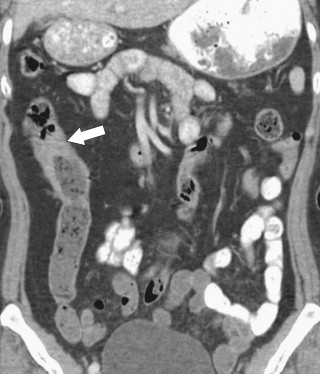

Portal colopathy is not strictly an inflammatory disease but is included here for completeness. Chronic liver disease with secondary portal venous hypertension can affect almost the whole GI tract from the esophagus and stomach (varices) to the small bowel (diffuse mucosal thickening) and colon. In the colon there may be variceal formation (similar to the mechanism in the stomach and esophagus) or diffuse vascular ectasia, which has a propensity for hemorrhage. Imaging may demonstrate diffuse colonic thickening secondary to increased venous pressure or hypoproteinemia ( Fig. 5-42 ). Direct evidence of variceal formation ( Fig. 5-43 ) may appear throughout the colon or be limited to the rectum, where it may present as hemorrhoids or rectal bleeding ( Fig. 5-44 ).

Figure 5-42, Axial ( A ) and coronal ( B ) contrast-enhanced CT in a 44-year-old man with cirrhosis and portal colopathy ( arrows ). There is associated ascites and splenomegaly ( small arrow ).